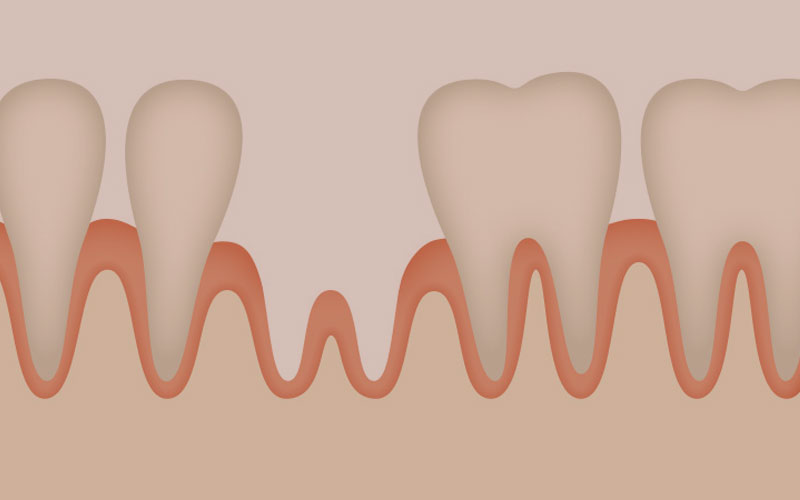

骨吸収

加齢などで口元が痩せて見えることがありますが、顎の骨が衰えて減ることで起こります。特に歯が抜けると、歯を支える役割を失った骨は衰えが早くなります。食べ物の咀嚼で与えられる刺激が、骨を保つ指令となっているからなのですが、歯を失うことで刺激を受けなくなり骨は徐々に減ってゆきます。これが骨吸収と呼ばれるものです。

周囲の歯への影響

歯を失った箇所の骨は、その歯だけを支えている訳ではありません。骨吸収が起こっている周りの歯にとっても、支えになっている骨が徐々に減っていきます。たとえ歯自体が健康だったとしても、土台からのぐらつきや揺れなど不安定になってしまいます。

骨吸収によって骨が失われた場合には、そのままではインプラントを埋入できるほどの骨量が無い場合があります。その場合は、上記にあるような増骨処置を行い、あらかじめ土台となる骨を確保したうえでインプラント治療を行います。

インプラント治療により、歯の根の代わりとなるものが顎の骨に埋め込まれます。埋め込まれてしばらくは、インプラントと骨との境目で、骨の吸収(破壊)と再生が繰り返され、徐々にあごの骨に結合していき安定するようになります。人工の歯の根とは言えインプラントは歯の根としての役割を果たすようになり、咀嚼などの刺激を受け、骨吸収のリスクを減らしていきます。